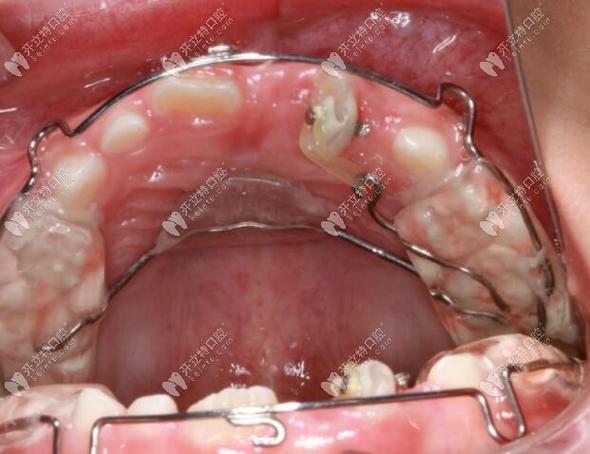

传统矫正需分阶段更换弓丝:先用镍钛圆丝排齐牙列,再用不锈钢方丝配合“扭转簧”“链状皮圈”等附件施加旋转力,通过“旋转-控根”两步法将牙冠与牙根同步调整;隐形矫正则需每1-2周更换一副牙套,每副牙套上设计“附件”(如小凸点)增强牙齿抓持力,计算机模拟确保每一步旋转角度在安全范围内;舌侧矫正因托槽位置特殊,需个性化定制弓丝与托槽,通过“三维力系统”精细控制牙齿移动。